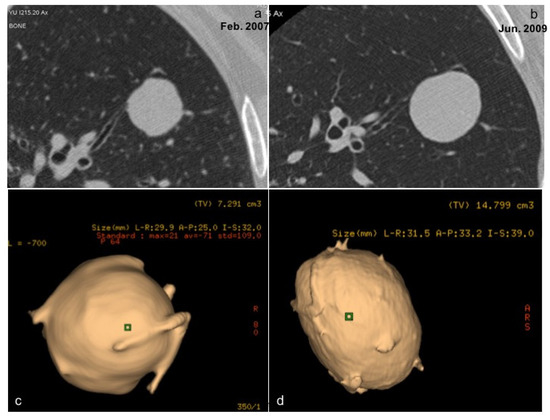

- Volterrani, L.; Mazzei, M.A.; Scialpi, M.; Carcano, M.; Carbone, S.F.; Ricci, V.; Guazzi, G.; Lupattelli, L. Three-dimensional analysis of pulmonary nodules by MSCT with Advanced Lung Analysis (ALA1) software. Radiol. Med. 2006, 111, 343–354. [Google Scholar] [CrossRef]

- Mazzei, M.A.; Scialpi, M.; Mazzei, F.G.; Giacobone, G.; Volterrani, L. Three-dimensional volumetric assessment with thoracic CT: A reliable approach for noncalcified lung nodules? Radiology 2010, 254, 634. [Google Scholar] [CrossRef][Green Version]